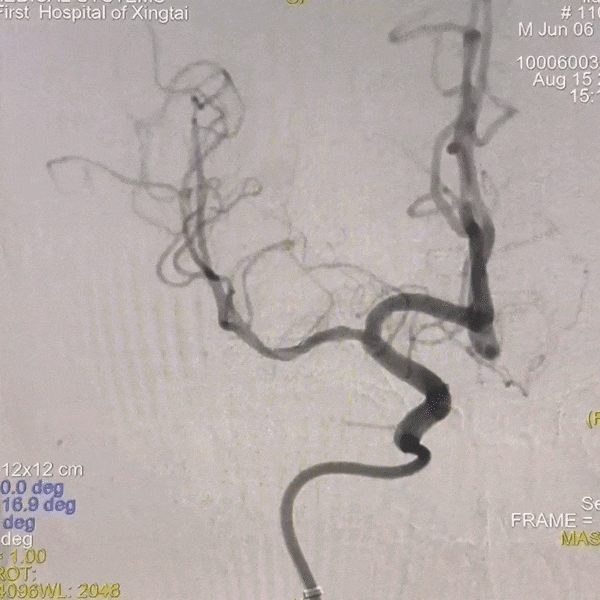

DSA提示患者右侧大脑中动脉狭窄率约95%;PWI提示右额颞顶叶低灌注。

动脉长鞘怎么置入一技之“长”丨经桡及经股困难入路应用赛诺神畅APEX TRA GC™导引导管建立通路病例合集_https://www.jmylbn.com_新闻资讯_第31张

动脉长鞘怎么置入一技之“长”丨经桡及经股困难入路应用赛诺神畅APEX TRA GC™导引导管建立通路病例合集_https://www.jmylbn.com_新闻资讯_第32张

头PWI

DSA

后撤微导管至右侧大脑中动脉M1段分叉处,路图下微导丝超选入右侧大脑中动脉M2段上干,跟进微导管,撤出微导丝,手推造影显示微导管在血管真腔内,再次送入微导丝,撤出微导管,沿微导丝送入2.0*15mm 球囊扩张导管,由远及近分次进行扩张,扩张后显示狭窄段较前明显好转。

术后情况

支架植入后造影提示残余狭窄约0%, 右侧大脑中动脉供血区供血较前明显改善,前向血流达到3级。患者麻醉复苏后无不适,恢复良好出院,继续双联抗血小板聚集及他汀类药物治疗。